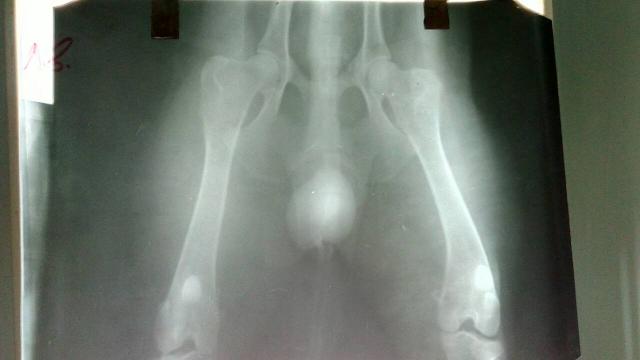

Начну с того, что не исключаю у Вашего пса дисплазию тазобедренных суставов. Думаю, что это она явилась причиной "шаркающей" походки с детства. Но в истории этой болезни она, по всей видимости, участия не принимает. Если Вы сделаете снимки суставов, то сразу выявите это заболевание. Думаю, тот факт, что собака плохо передвигалась, не связан с процессом в суставах, а с ухудшением общего состояния вследствие интоксикации, вызванной инфекционным процессом в предстательной железе. При гнойных процессах в организме животных их состояние быстро и значительно ухудшается. О происхождении абсцесса в простате ничего не могу сказать, это вопрос к ветеринарной медицине.

Я всё-таки, как онколог, насторожена в плане онкопатологии, надеюсь, я ошибаюсь, но не могу исключить злокачественную опухоль простаты. У Макса оба яичка опущены, если нет, то второе тоже часто даёт онкологию. Исключайте опухоль и поднимаете иммунитет! Сейчас ваша основная задача поддержать иммунную систему: хорошая кормёшка, пробиотики, никаких переохлаждений, витамино-минеральные комплексы и иммуномодуляторы. Заработает иммунитет и инфекция уйдёт.